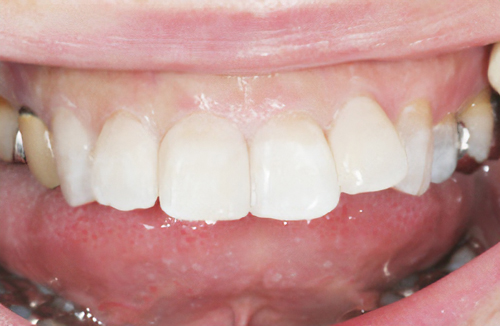

術前

-

術後